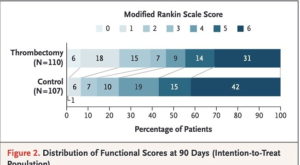

24時間以内の脳底動脈閉塞例に対し、あまり大きな虚血コアがなければ血栓回収療法実施で転帰は改善します。PC-ASPECT、Pons-Midbrain Indexなどの画像評価方法、確認が必要ですね!

※詳細は以下の画像をクリックしてご覧ください。